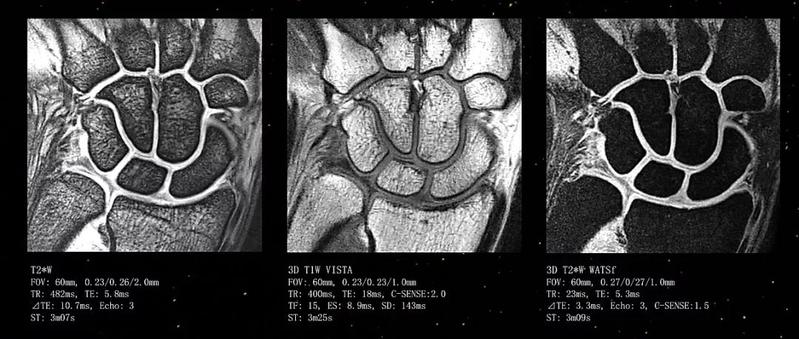

更清晰的成像技术

图像分辨率更高,成像更清晰,对心血管系统、中枢神经系统,骨关节,肌肉等系统的疾病检查最具优势,有利于捕捉到微小病灶,提高病灶检出率,为疾病的早期诊断提供依据,对临床诊疗具有重大帮助。

肌肉骨关节系统:可清晰显示关节软骨、韧带、肌肉和肌腱,在关节病变的诊断中明显优于CT,在一定程度上可代替有创性的关节镜检查。